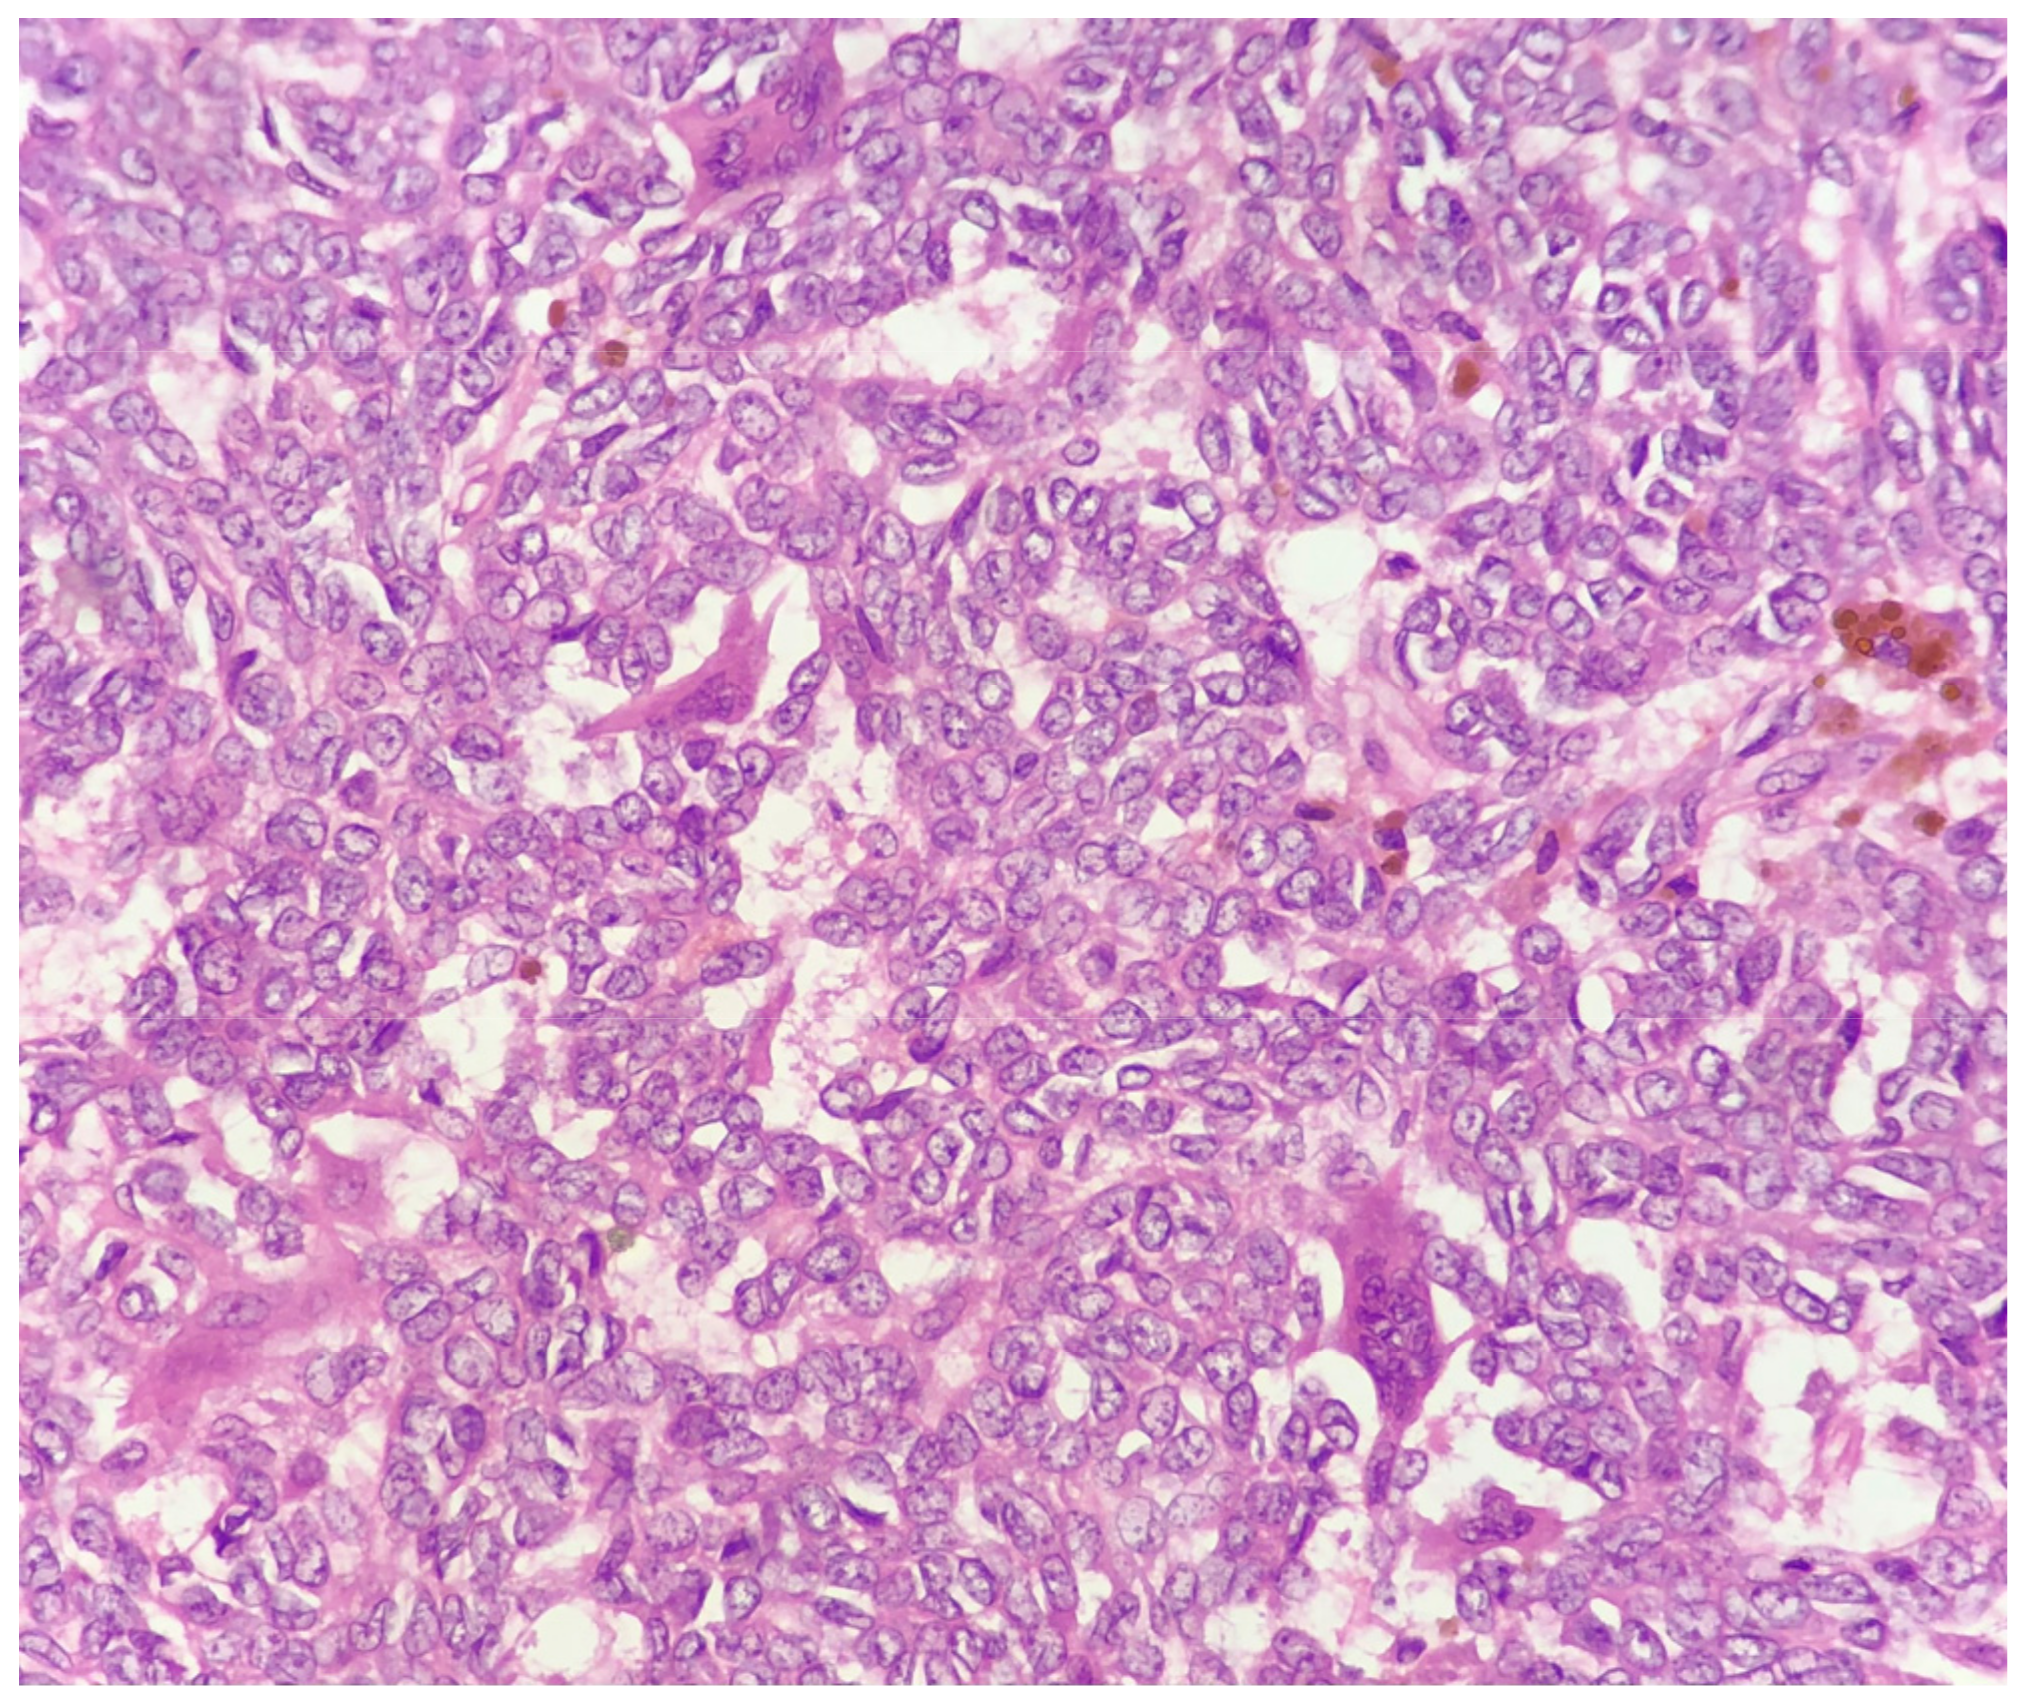

At histology, it was composed of spindle and round cells with a scarce eosinophilic and clear cytoplasm, as well as vesicular nuclei with small to medium-sized nucleoli. The cells were arranged in sheets and nests and showed a vaguely pseudo-alveolar architecture. Few osteoclast-like giant cells were also present (Figure 4).

Figure 4.

Few osteoclast-like giant cells are present within the neoplastic population (H&E 40×).